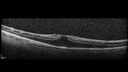

Paclitaxel induced cystoid macular edema - reversed when chemo stopped25 views74 year old retired physician About 2-3 weeks ago there was gradual vision loss in the right eye. The patient was seen by an ophthalmologist who saw macular swelling and injected vabysmo. He has been on chemotherapy (Carbiplatin and Carboxytaxol for 2 cancers - advanced prostrate diagnosed 2019 - has had brain surgery AND squamous lung cancers treated with radiation)

Medical Hx: Prostate cancer (Onset: 2018). Pulmonary and bone cancer metastatic. Brain cancer metastasized from prostate cancer.

Surgical Hx: Right frontal & Frontoparietal Craniotomy (Onset: 2024). Appendectomy. Hemorrhoidectomy. Herniorrhaphy. Prostate. Systemic Meds: Chemotherapy. Radiation. Eligard Every 3 Months 22.5 MG per 0.375 ML Prefilled Syringe. MIRALAX prn. Tums Freshers 500 MG Chewable Tablet. Vitamin D. XGEVA.

VA OD: Dcc20/125+1

VA OS: Dcc20/125-2

TP: OD:12 OS:15Aug 17, 2025